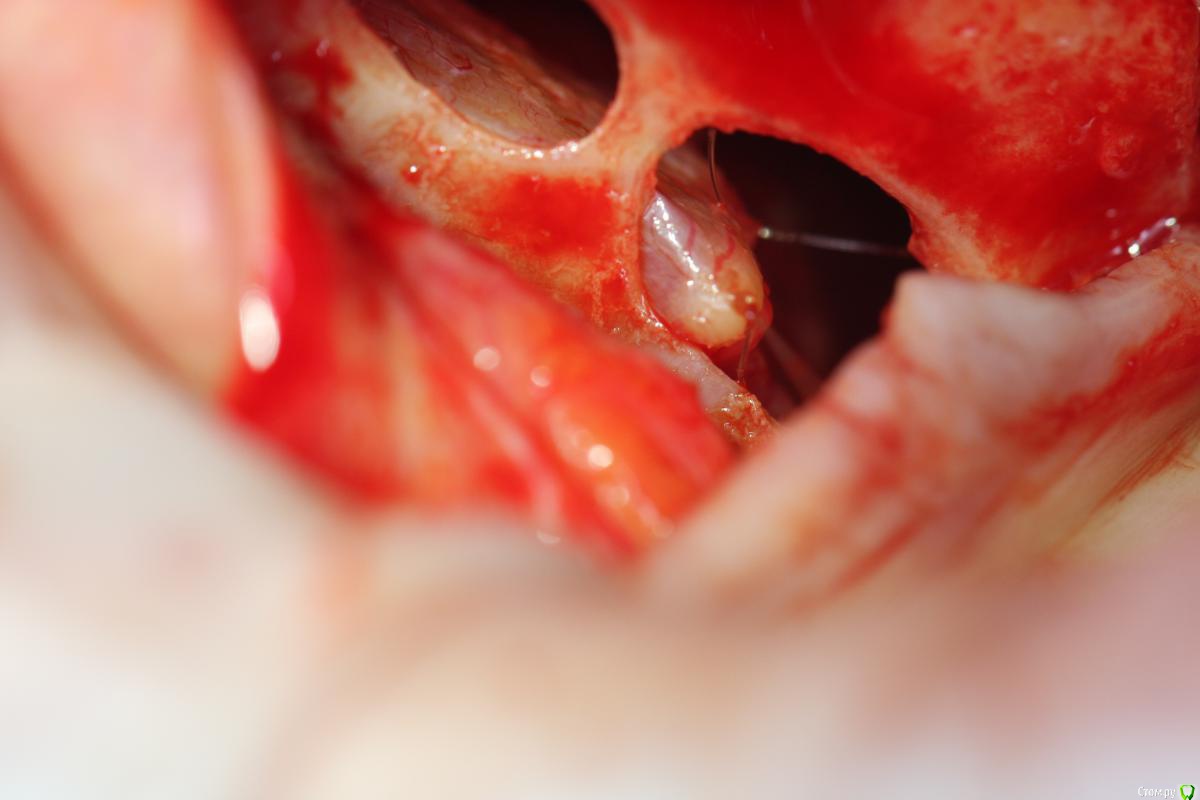

Rafael_Gogyan Опубликовано 5 октября, 2016 Поделиться Опубликовано 5 октября, 2016 (изменено) http://s017.radikal.ru/i413/1610/a0/f15e3aa84072.jpg http://s017.radikal.ru/i443/1610/61/22c536a171c3.jpg это то, что попало в камеру на последнем фото слизистая пришита к костной стенке Изменено 5 октября, 2016 пользователем Rafael_Gogyan 5 Ссылка на комментарий